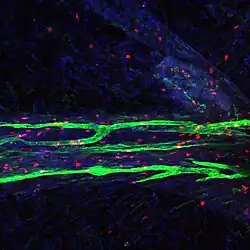

In transgenic mice containing Prox1-GFP or Vegfr3-LacZ reporter genes, the lymphatic vessels may be visualized by fluorescent microscopy or after X-gal staining, respectively.[2]

The meningeal lymphatic system is composed of a network of vessels along the dural sinus in the dura which express lymphatic endothelial cell marker proteins, including PROX1, LYVE1, and PDPN. The vessels extend along the length of both the superior sagittal and transverse sinuses and directly connects to the deep cervical lymph nodes.[1] These meningeal lymphatic vessels drain down and exit the skull along the dural venous sinuses and meningeal arteries. Meningeal lymphatic vessels also drain out of the skull alongside cranial nerves and through the cribriform plate. Molecular profiling indicates that the vessels are conventional lymphatic vessels: they express high levels of PROX1, LYVE1, PDPN and VEGFR3, but low levels of PECAM1. Meningeal lymphatic vessels absorb cerebrospinal fluid and drain into the deep cervical lymph nodes.[2]

Like peripheral lymphatic vessels, the meningeal lymphatics serve both the tissue drainage and immune cell trafficking functions of the lymphatic system. Multiphoton live imaging experiments performed on anesthetized mice have demonstrated that the meningeal lymphatics are capable of draining fluorescent dyes injected intracisternally into the CSF, indicating that the meningeal lymphatics are capable of draining fluid from their surrounding environment. Histological analysis revealed that the meningeal lymphatics constitutively contain T cells, B cells, and MHC class II-expressing myeloid cells, demonstrating that meningeal lymphatic vessels are capable of carrying immune cells.[1]